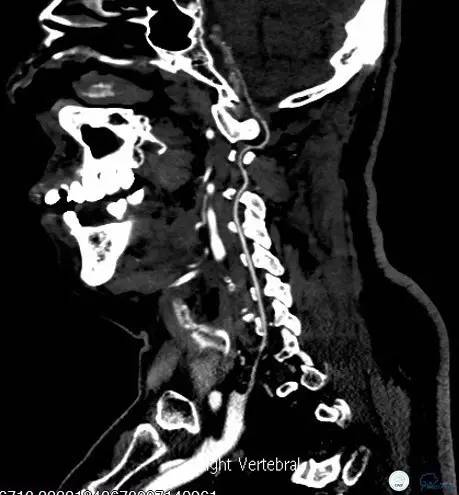

头颈部CTA(图3-6):双侧椎动脉远端及基底动脉近端混合斑块、管腔中-重度狭窄,双侧大脑后动脉纤细。

图6